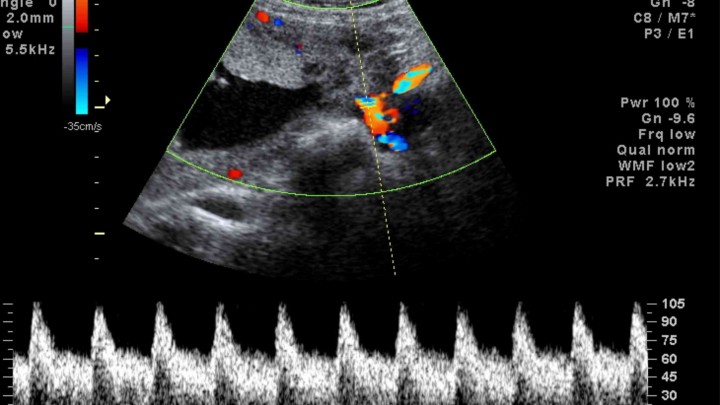

El diagnóstico exacto se hace a través del ecocardiograma (sumado al examen del médico y otros estudios como el electrocardiograma) y el tratamiento está a cargo del cardiólogo infantil.